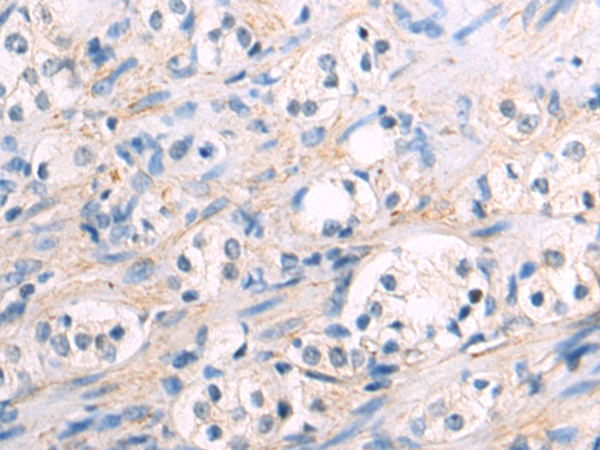

分类: 科研抗体货号: P12772别名: NAG14; NGL-2应用: IHC反应种属: Human, Mouse, Rat